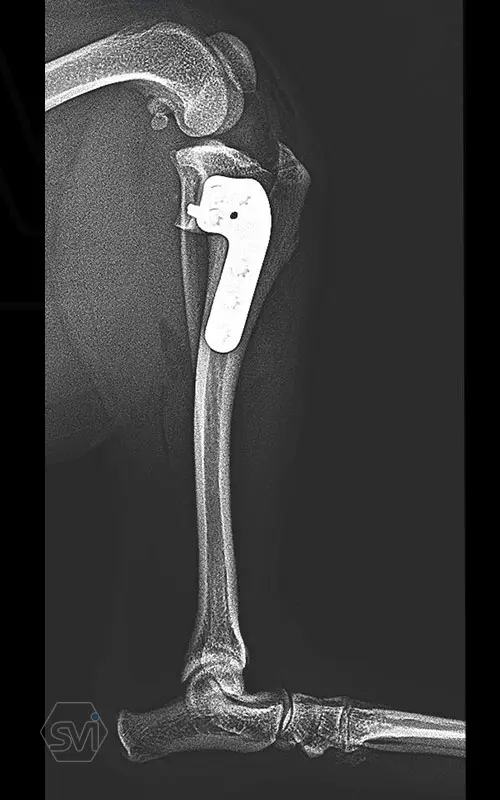

Multifunctional symmetrical long polyaxial locking plate - designed for the treatment of fractures close to joints

A special member of the polyaxial locking plate family is the multifunctional long plate, which is an extended version of the well-known symmetrical TPLO plate, with a 5-3 hole distribution. The plate also received a DCP hole to be able to create compression, and there is a mini-hole on the head end to facilitate the placement of the temporarily used K-nail. The burrs on the side facing the bone surface are intended to reduce the contact surface between the plate and the bone (limited contact).

The plate is a member of the large polyaxial locking family, suitable for 2.7-3.5-4.0 mm screws. We recommend it for fixaton of fractures close to joints, wedge osteotomies with axis correction (closing and opening), or for CWTO operations.